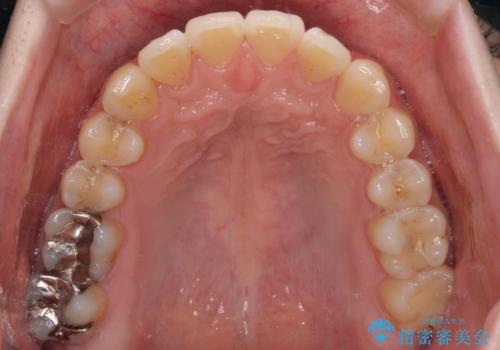

インビザライン・ライトによる矯正治療の後戻り改善

- 矯正治療の後戻りを気にして来院された患者様です。

後戻りは軽微でしたので、インビザライン・ライトにより矯正治療を行うこととしました。

再矯正後の後戻りを防ぐため、歯列排列後に、下顎前歯はワイヤーによる固定を行いました。

下顎前歯の歯列を動かないようにしておくことで、上顎前歯の後戻り防止にも効果を発揮します。